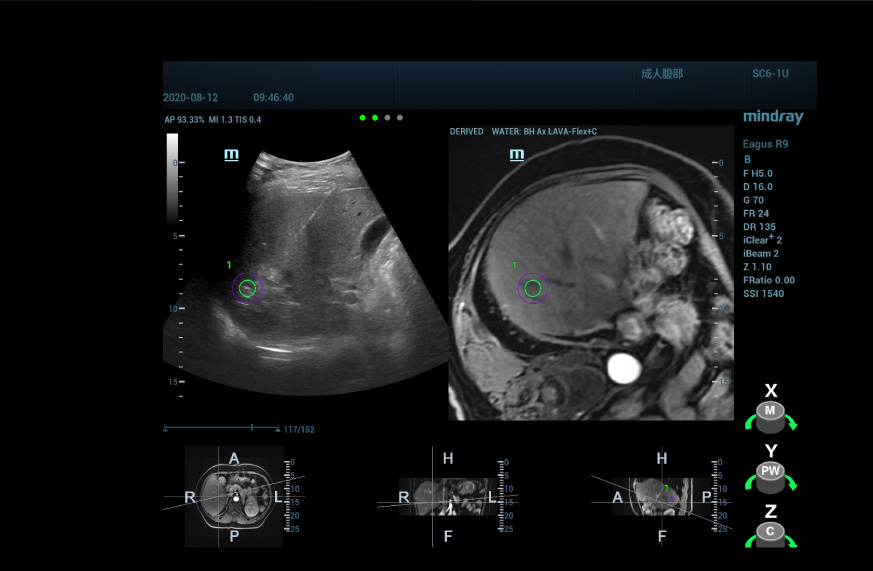

Mindrayâin uHit Fusion ÞrÞnÞnÞ kullanarak, ?ok modlu bir fÞzyon tekni?inden yararlan?ld???nda, MR bilgileri ultrason g?rÞntÞsÞyle bir araya getirilir ve b?ylelikle MR T1WI geli?imiyle g?sterilen anormal derecede geli?mi? nodÞllerin yerini g?rebiliriz. MR d???nda, ek uzamsal konumland?rma bilgileriyle, lezyonun yerini yÞksek derecede gÞvenle belirleyebiliyoruz.

Ultrason/ultrason fÞzyon g?rÞntÞsÞ i?in, lezyonun prosedÞr ?ncesi 3B ultrason verilerini al?yor ve bunu ger?ek zamanl? 2B g?rÞntÞ ile birle?tiriyoruz, b?ylelikle prosedÞr ?ncesi de?erlendirmeden elde edilen bilgilerden tam olarak yararlan?labiliyor ve tekrar ultrasonografi yap?larak lezyonun konumu ve yap?s? do?rulanabiliyor.

Tedavi esnas?ndaki ka??n?lmaz solunum hareketleri ve beklenmeyen vÞcut hareketleri i?in, birle?tirme esnas?nda pozisyon de?i?ikliklerini dÞzeltmek ve ablasyon ?ak??t?rmas?n? daha do?ru ve kararl? hale getirmek Þzere, hareket dÞzeltme ve solunum kompanzasyonu i?levlerini sunduk.